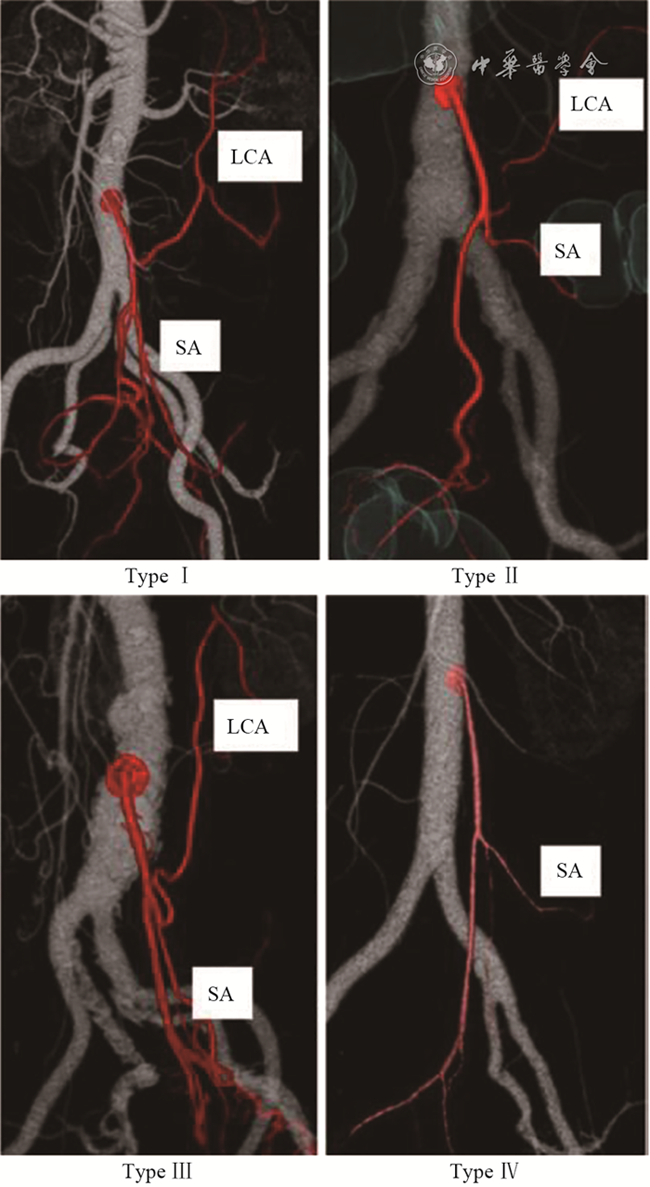

IMA分支有许多不同的分型,LCA既可单独起源于IMA,也可与乙状结肠动脉(sigmoid artery,SA)及直肠上动脉(superior rectal artery,SRA)共干,或与SA共干。Ⅰ型,直、乙共干型,LCA单独发出,约占38%;Ⅱ型,左、乙、直全共干型,约占45%;Ⅲ型,左、乙共干型,约占12%;Ⅳ型,无左型,约占5%。绝大多数LCA走向结肠脾曲(图2图3[6],但有约5%的LCA直接汇入远端降结肠边缘弓,5%的患者LCA可缺如;LCA也可走行与乙状结肠靠近,再沿降结肠上行至结肠脾曲[3]。副左结肠动脉(ALCA)出现与IMA变异、直径和走行有关。156例尸解发现:14.5%存在ALCA的同时,12%的LCA缺如、变细,走行更靠近SA[10]

图2 左结肠动脉的分支类型(引自参考文献6)。Ⅰ型,直、乙共干型,LCA单独发出(38%);Ⅱ型,左、乙、直全共干型(45%);Ⅲ型,左、乙共干型(12%);Ⅳ型,无左型(5%)